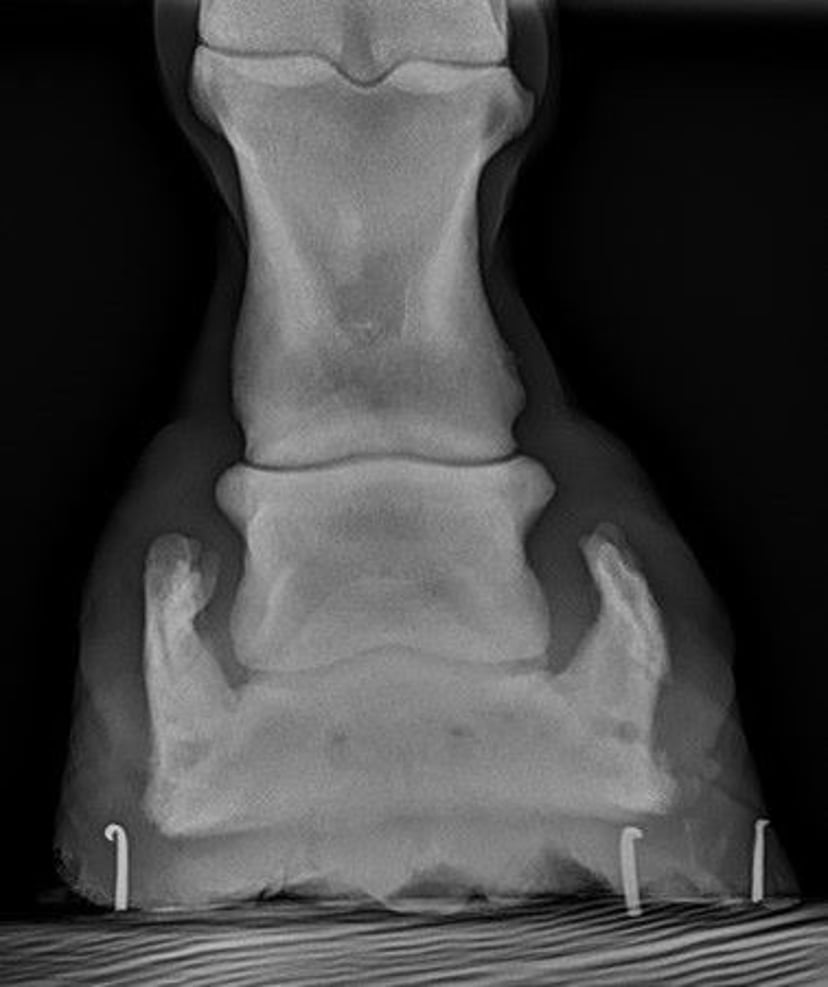

Dorsal-to-palmar radiographic image showing bilateral ossification (arrows) of the collateral cartilages of the distal phalanx in a horse.